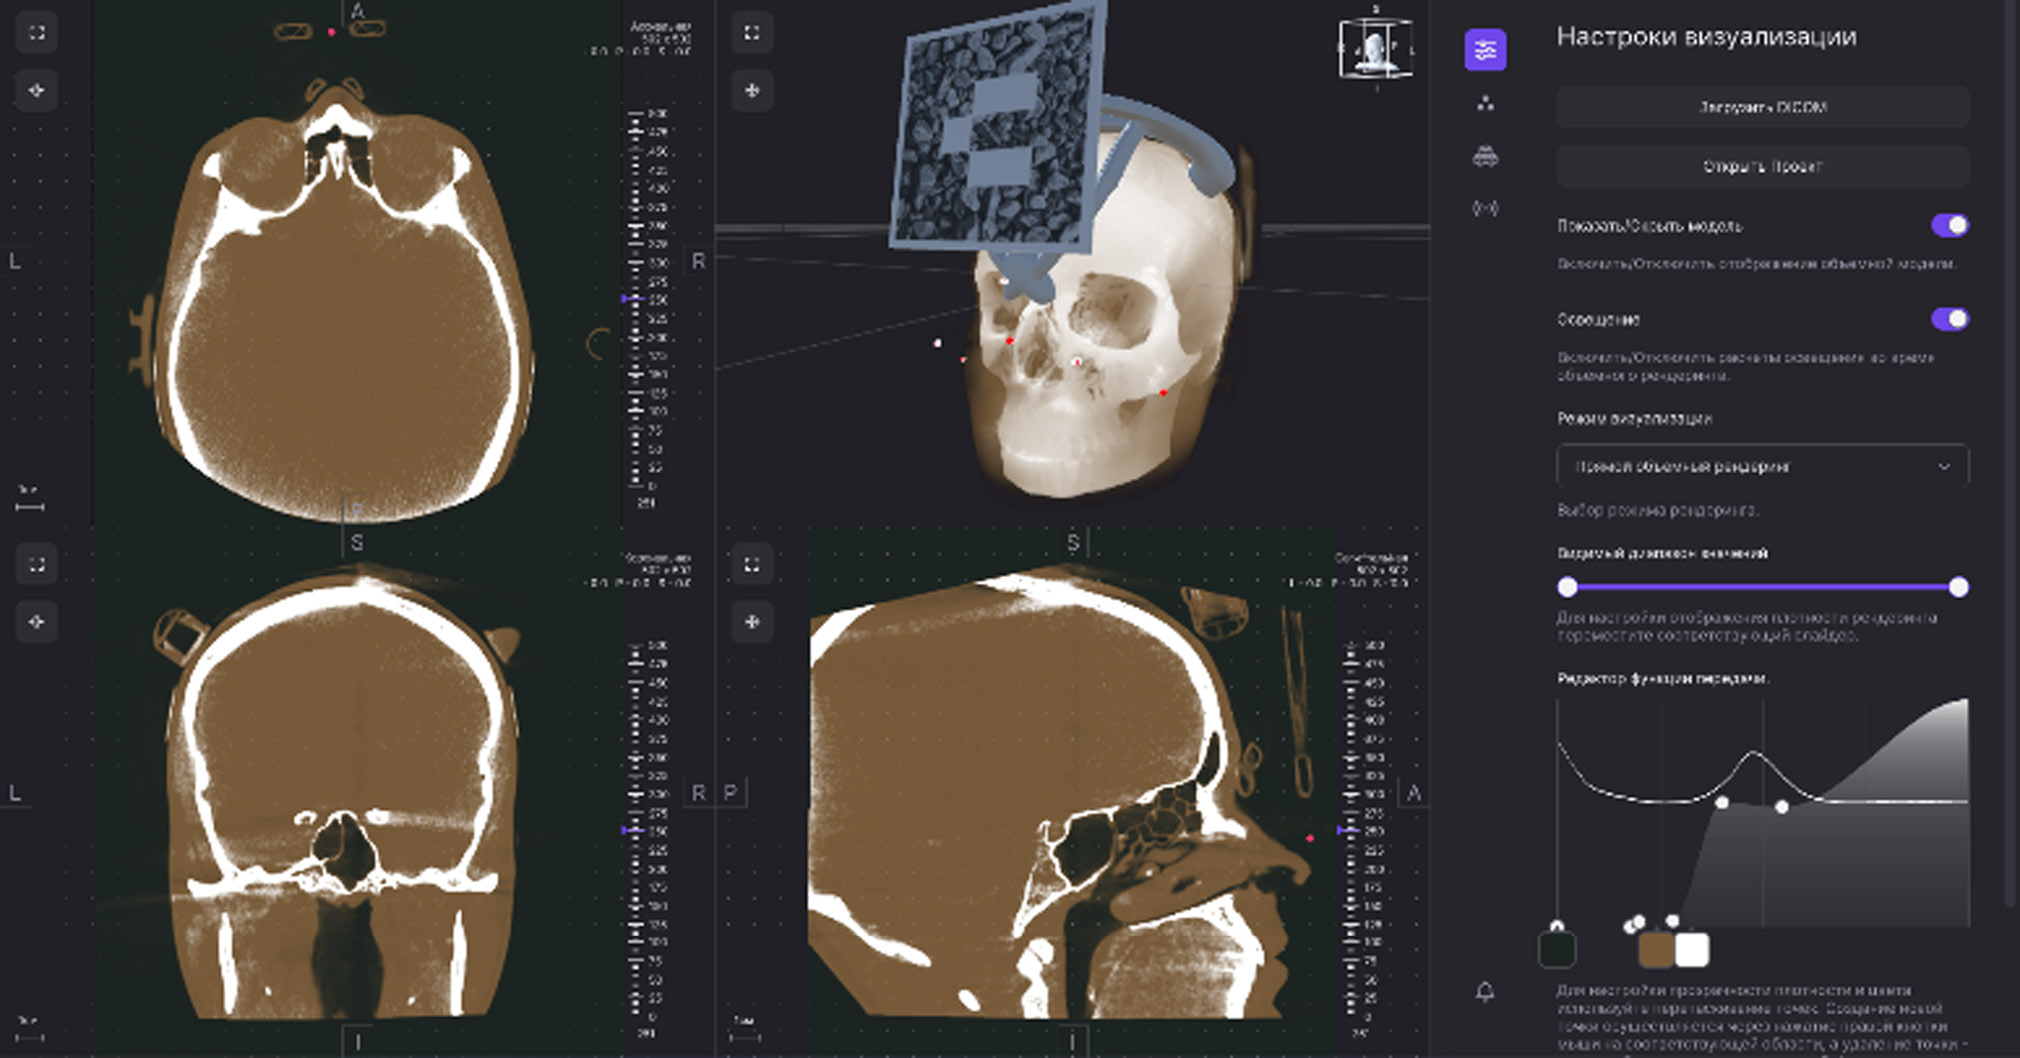

Непосредственно после КЛКТ металлические рентгеноконтрастные шарики сегментировали в программе Slicer3D, а изображение калибровали и загружали в очки дополненной реальности с помощью программы Medgital Vision Editor (рис. 2).

Рис. 2. Этап сегментации в программе Medgital Vision Editor.

Была выполнена КЛКТ моделей с последующей сегментацией рентгеноконтрастных меток и загрузкой сегментированных изображений в AR-очки в программе Medgital Vision Editor (рис. 7).

Рис. 7. Рентгеноконтрастные метки на этапе сегментации в программе Medgital Vision Editor.

- Сегментация 3D-изображения зоны вмешательства (новообразования, кисты, зубы и инородные тела). Для сегментации изображений и создания 3D-моделей использовали специальное программное обеспечение Medgital Vision Editor, предназначенное для обработки медицинских 3D-изображений.

В программу загружали КЛКТ-изображения в формате DICOM и изображения, полученные методом оптического сканирования на предоперационном этапе. После совмещения DICOM- и STL-файлов хирург определял зону вмешательства и начинал построение 3D-проекции. Зона вмешательства представляет собой область, в которой локализованы новообразования, кисты или ретенированные зубы. В зоне вмешательства предусматривали достаточное расстояние до всех прилежащих анатомических структур, таких как нервы и корни зубов. Следующим шагом была сегментация зоны вмешательства. Сегментацию изображения выполняли вручную или полуавтоматически (рис. 13).